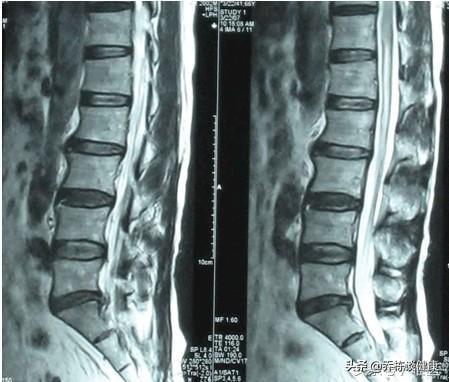

Le spondylolisthésis lombaire est un large éventail d'affections qui ne sont pas clairement décrites par les patients ; prenons donc l'exemple de la protrusion lombaire la plus courante.

La colonne vertébrale n'est pas un tout, il y a plusieurs vertèbres et disques intervertébraux, et nous parlons principalement des disques intervertébraux, qui sont divisés en deux parties, le "nucleus pulposus" et l'"annulus fibrosus", et la soi-disant hernie se réfère au fait que le nucleus pulposus se brise à travers l'annulus fibrosus, puis s'écoule hors de celui-ci pour irriter et opprimer les racines nerveuses et la moelle épinière, provoquant ainsi divers symptômes. Le terme "hernie" désigne le fait que le noyau pulpeux traverse l'anneau fibreux et s'en échappe, irritant et comprimant les racines nerveuses et la moelle épinière.

Cette hernie se produit en raison de l'âge, de la dégénérescence discale, mais une mauvaise posture et le fait de soulever des objets lourds peuvent accélérer ce processus, les patients eux-mêmes en raison de deux ans de repos, réduisent la hernie discale sur la racine nerveuse causée par l'irritation, atténuent le degré d'œdème et la réponse inflammatoire de la racine nerveuse, à cette époque, si l'on est forcé de porter des objets lourds, il est probable que la stabilisation de l'état se reproduise à nouveau, l'émergence de la douleur lombaire et de la jambe affectant la vie de la cause de la hernie. C'est simple :

Le repos ne fait que réduire la réponse inflammatoire, mais la rupture de l'anneau fibreux demeure, et si vous n'appliquez pas la bonne pression, vous pouvez également permettre à la moelle de s'écouler et d'irriter et de comprimer la racine nerveuse, et les symptômes réapparaissent.